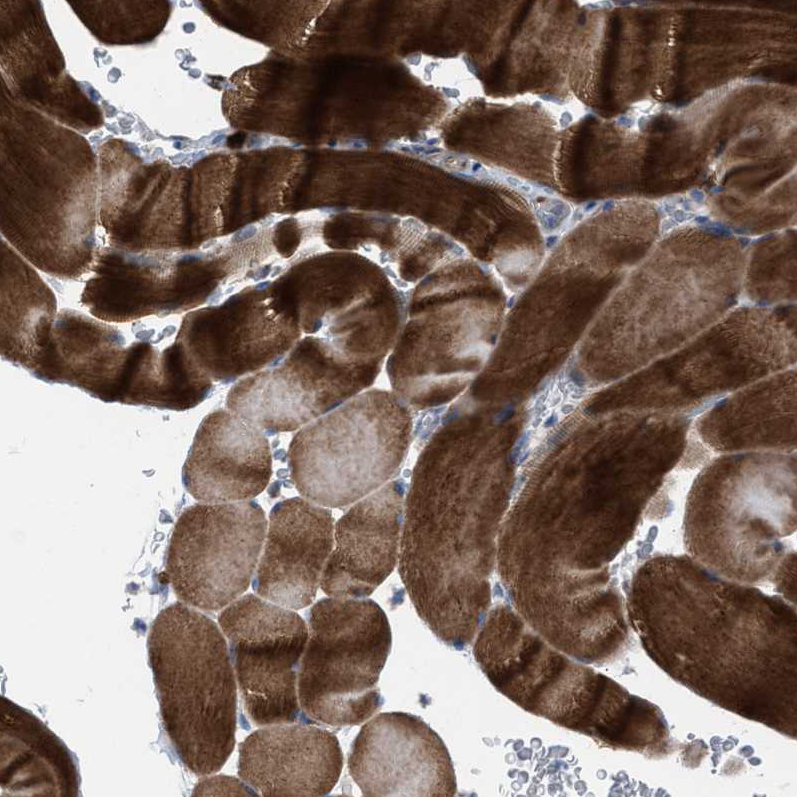

Immunohistochemical staining of human kidney shows strong membranous positivity in cells in tubules.